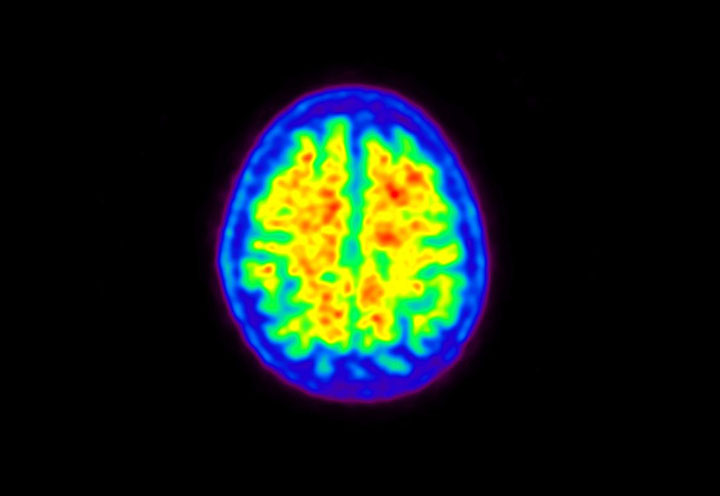

Head / Case5 : Amyloid

Courtesy : Kindai University Hospital

- Imaging protocol

- Injected dose: 4.27 MBq/kg, 18F-Flutemetamol

- Uptake time: 99 minutes

- Scan time: 20 minutes